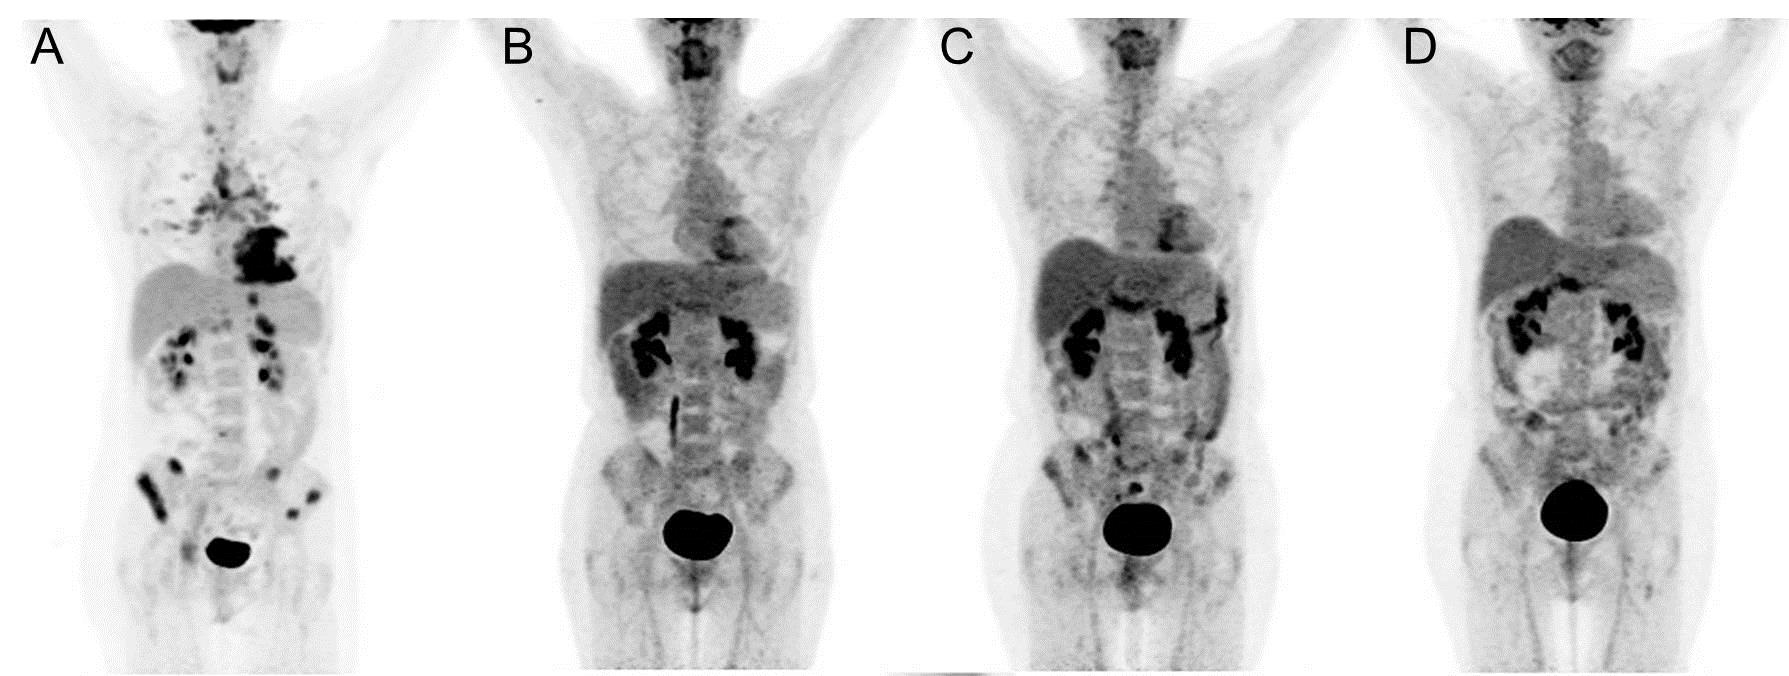

Диагностика лимфомы Ходжкина с помощью ПЭТ и КТ

Раздел: Светлые идеи